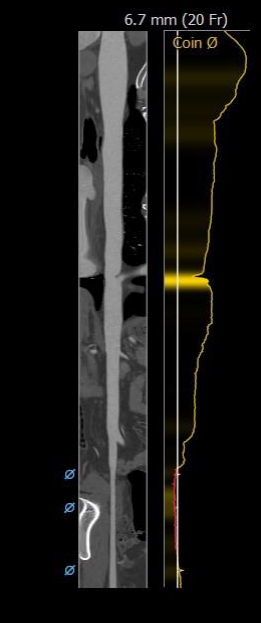

主动脉根部评估

根部概览

瓣上分析&心室大小分析